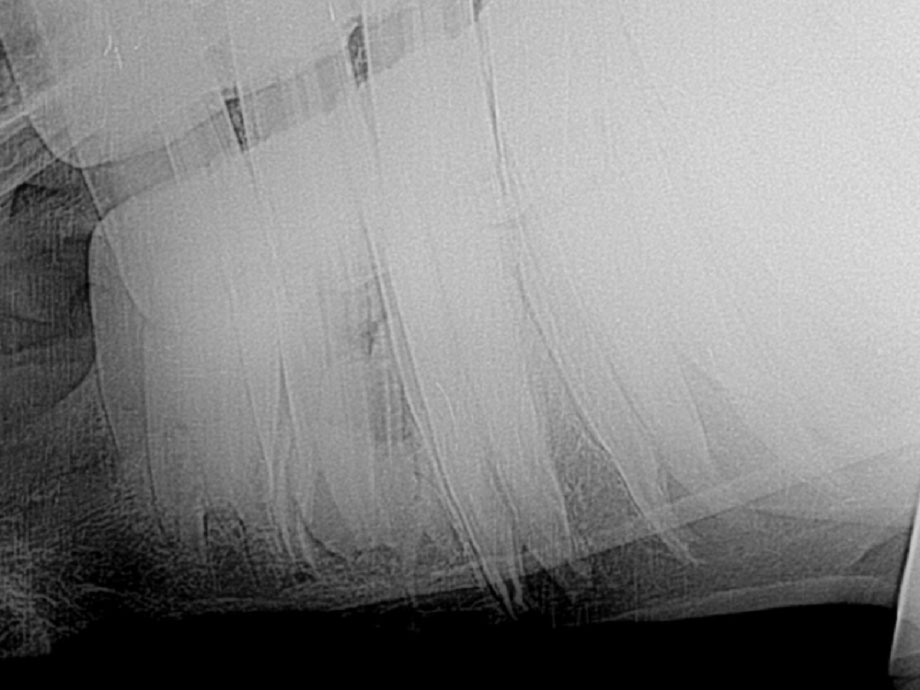

A 16 gauge needle was inserted in the proposed surgical site under the 307 and then radiographed to determine the exact location of entry for repulsion. It is necessary for the placement of the stieman to be directly in the middle of the root fragment for successful repulsion. The horse was sedated and the inferior alveolar nerve was blocked. This nerve block desensitizes all of the teeth and immediate surrounding structures only. Lidocaine was infused into the cheek and distal mandible in the area of the 307 to complete the nerve block for this standing procedure. A small biopsy punch was used to remove the skin and under lying tissue, including the periosteum. An 1/8th inch stieman pin with a trocar point was tapped through the distal mandible at the exact location under the 307 with a surgical mallet. A full mouth speculum is used to open the mouth to allow an assistant to place a finger on the root fragment while the stieman pin is advance to confirm proper positioning of the pin and to communicate with the surgeon concerning movement of the fragment during the procedure. Once the pin contacts the center of the fragment, a vibration will be noted by the assistant as the pin is tapped. In this case, the tooth root was repulsed intact without any portion of the root being fractured during the procedure. Post radiographs were taken to confirm complete extraction of the tooth.